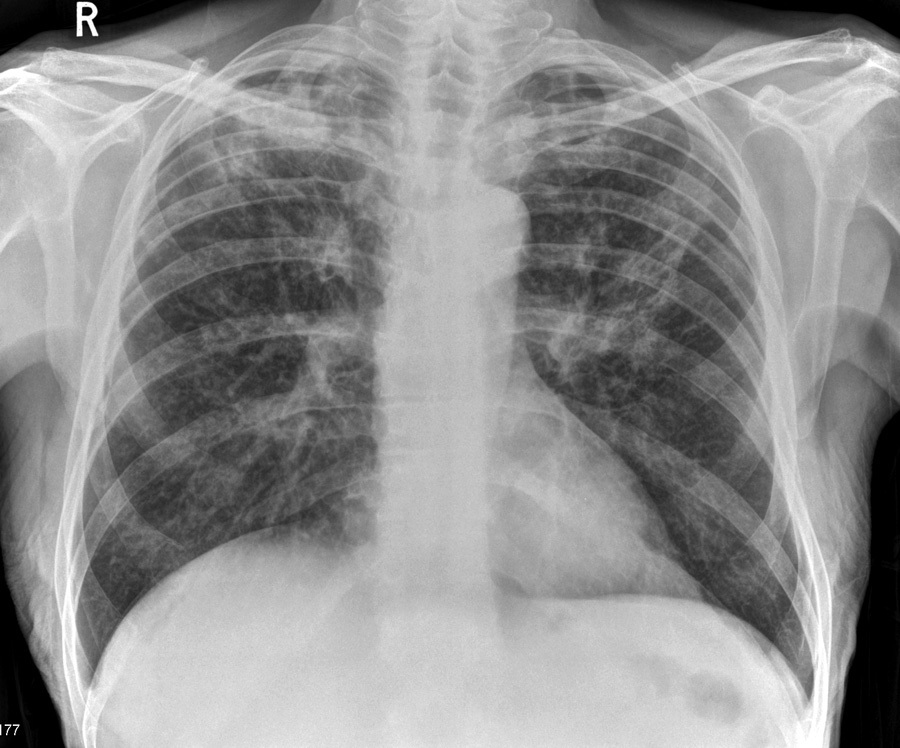

Coin or Cannonbal lesions on CXR?

Pulmonary mets

Most likely diagnosis?

chest radiograph shows bilateral ill defined upper lobe infiltrates/consolidation.

Most likely diagnosis: Tuberculosis